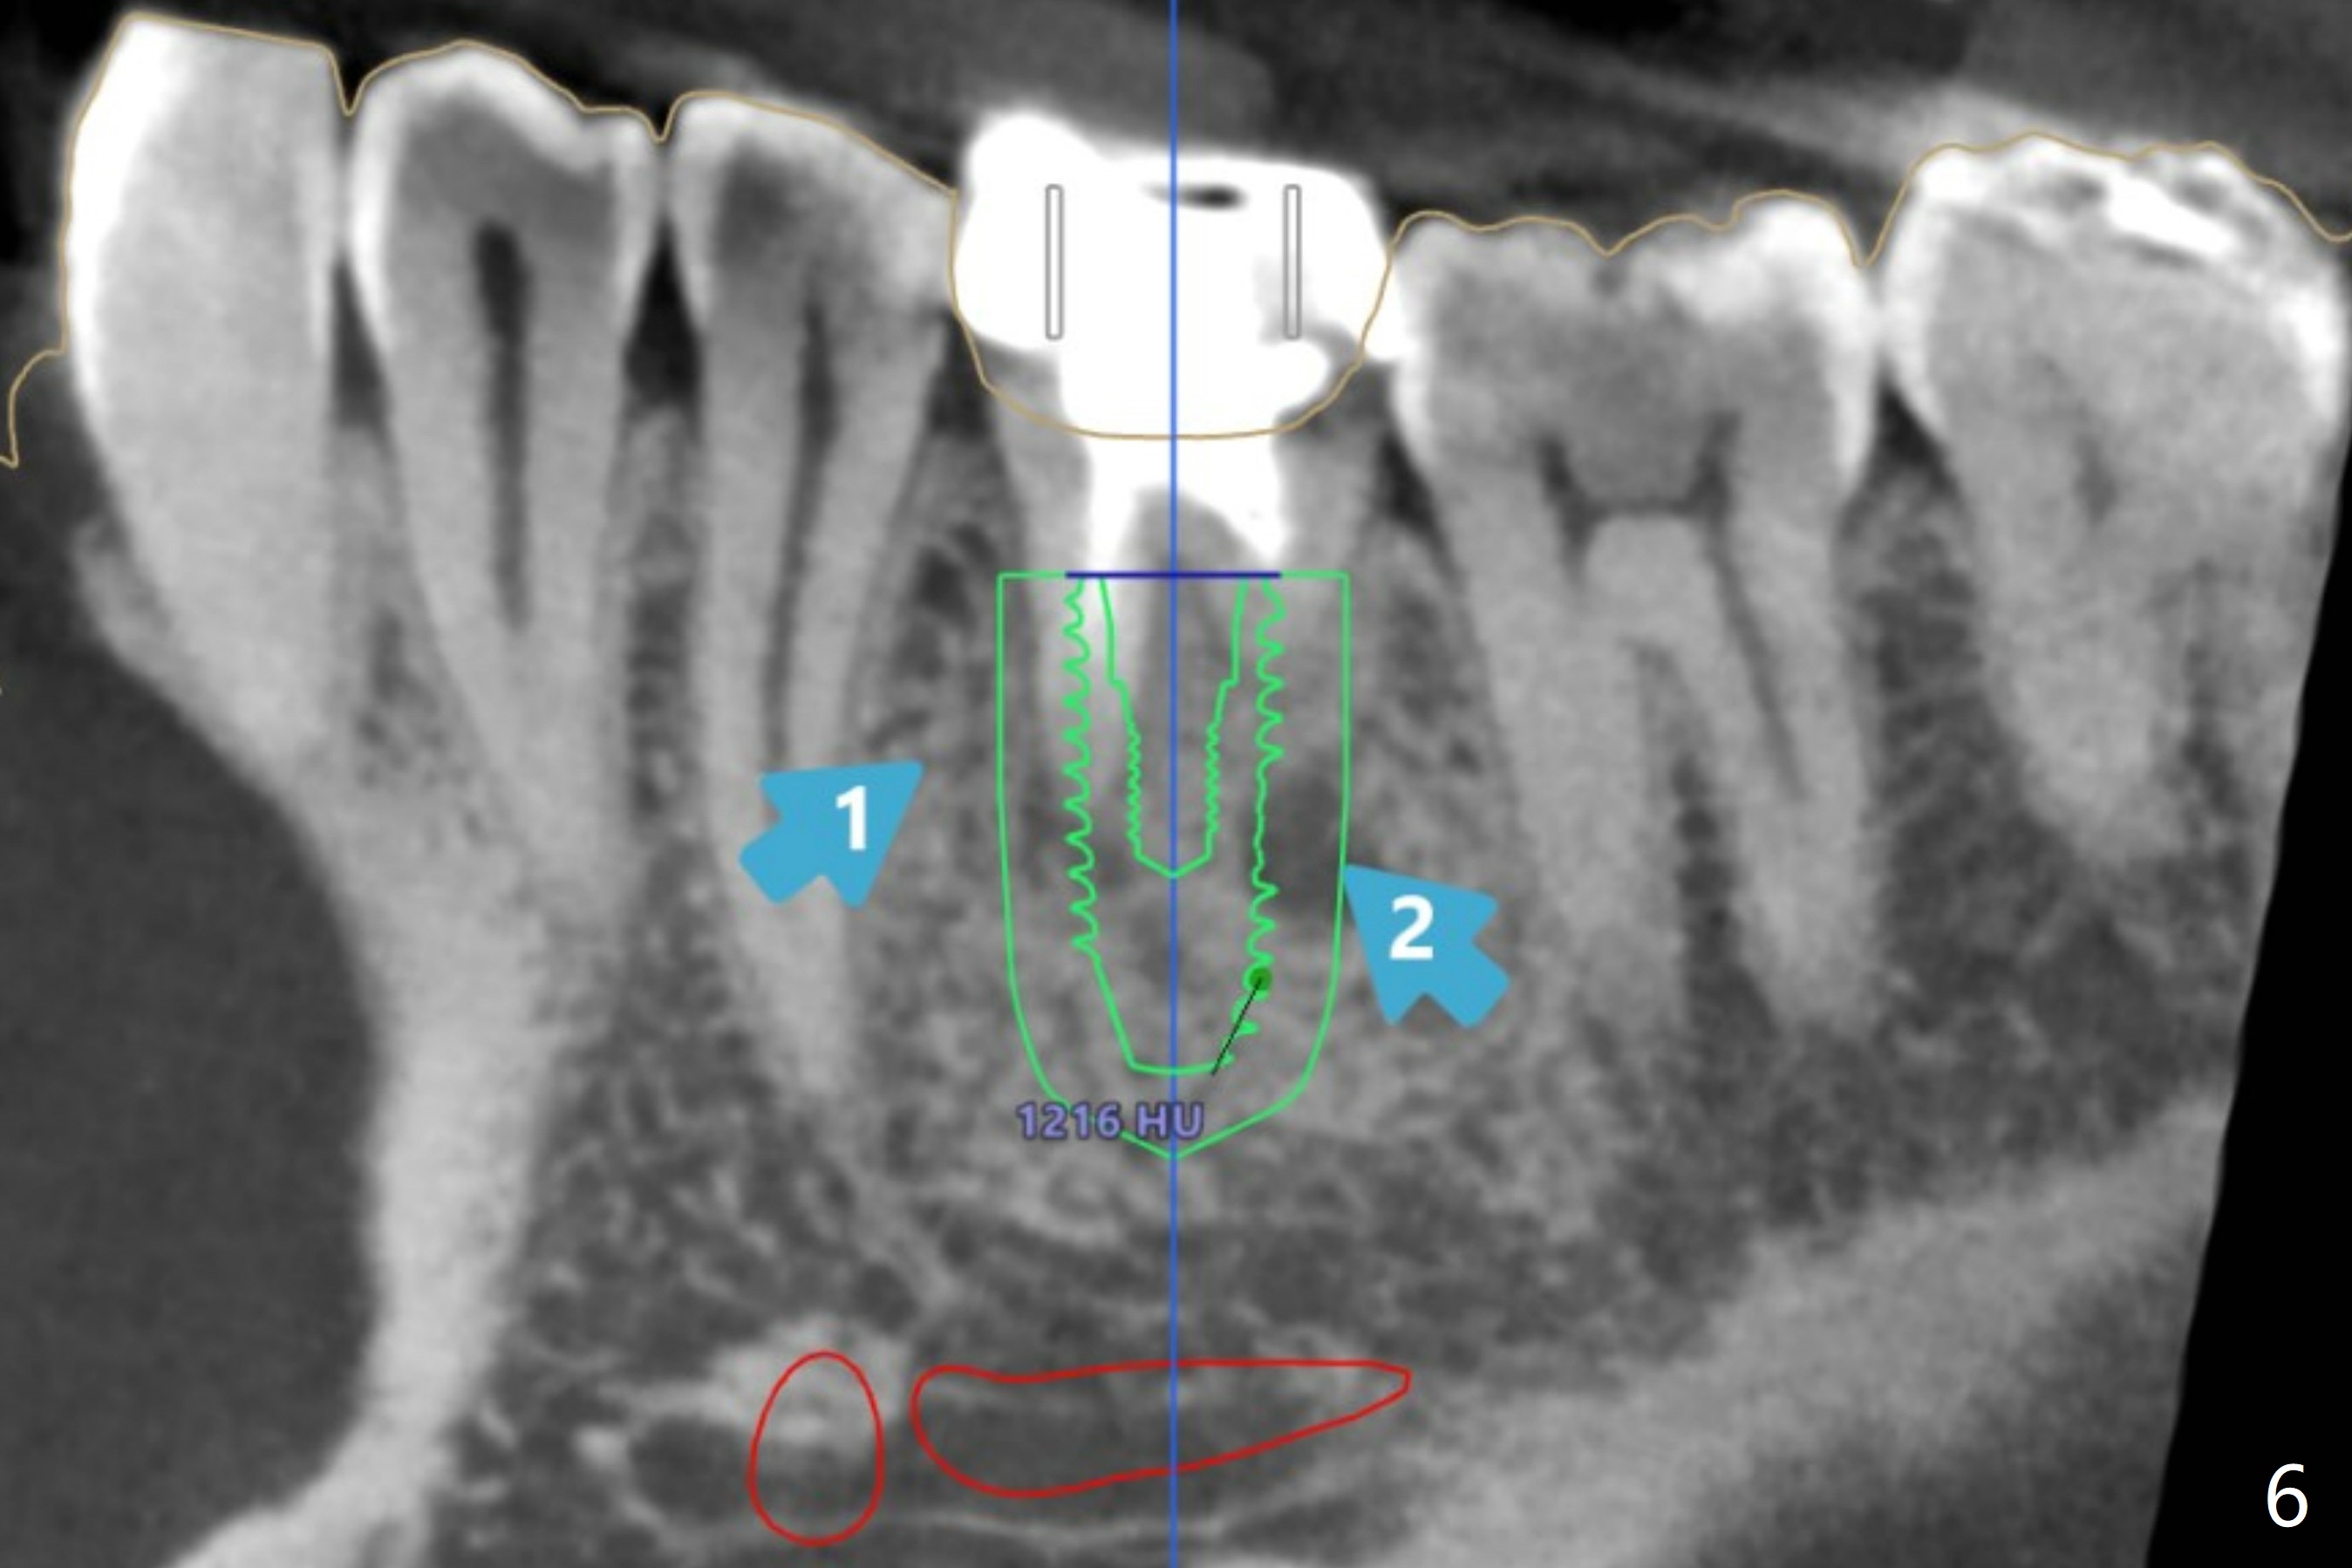

A 54-year-old man decides to extract the tooth #19 because of failure of RCT in the disto-lingual long curved root. Since it is difficult to drill through the roots, the latter will be removed. Use 2.2 mm drill to reach the depth first, look for deviation and take PA. Prepare cowhorn, surgical handpiece and proximators. PRFx1. Use 4.5x11.5 mm drill before placing 5.5x11mm IBS implant.